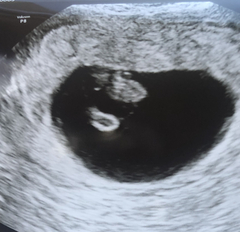

MumToBeMaz · 31/12/2020 11:40

Well, everything looks great they said!

They can see the yolk sac and fetal pole and mentioned that it looks like it's buried in there nice and deep.

Measuring perfect so far too.

Still early but it's looking a lot healthier than our last pregnancy. Keeping our fingers crossed.

5 week scan